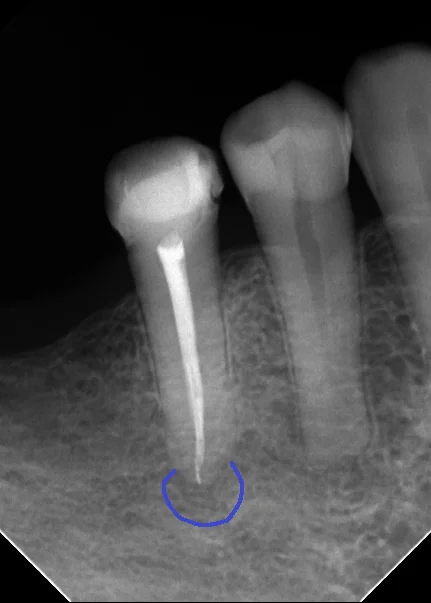

今回のケースでは根の先にそこそこなサイズの膿が溜まっている様子(青い丸の部分)

根の先には骨がしっかりと出来てくれています。(青い丸の部分)

膿があった影も完全に消失することが出来ましたね。